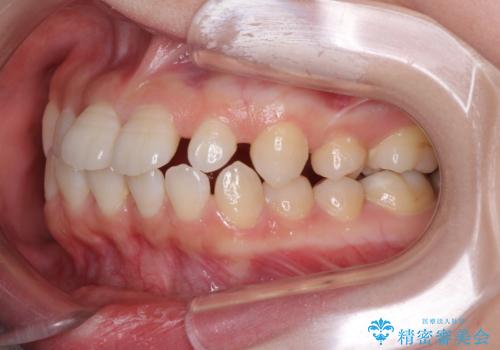

- 歯の欠損による隙間だらけの歯並びを気にして来院された患者様です。

上顎左右1本ずつ欠損していたため、歯列矯正により欠損部位にスペースを集め、その後欠損部位をインプラントにて補綴することとしました。